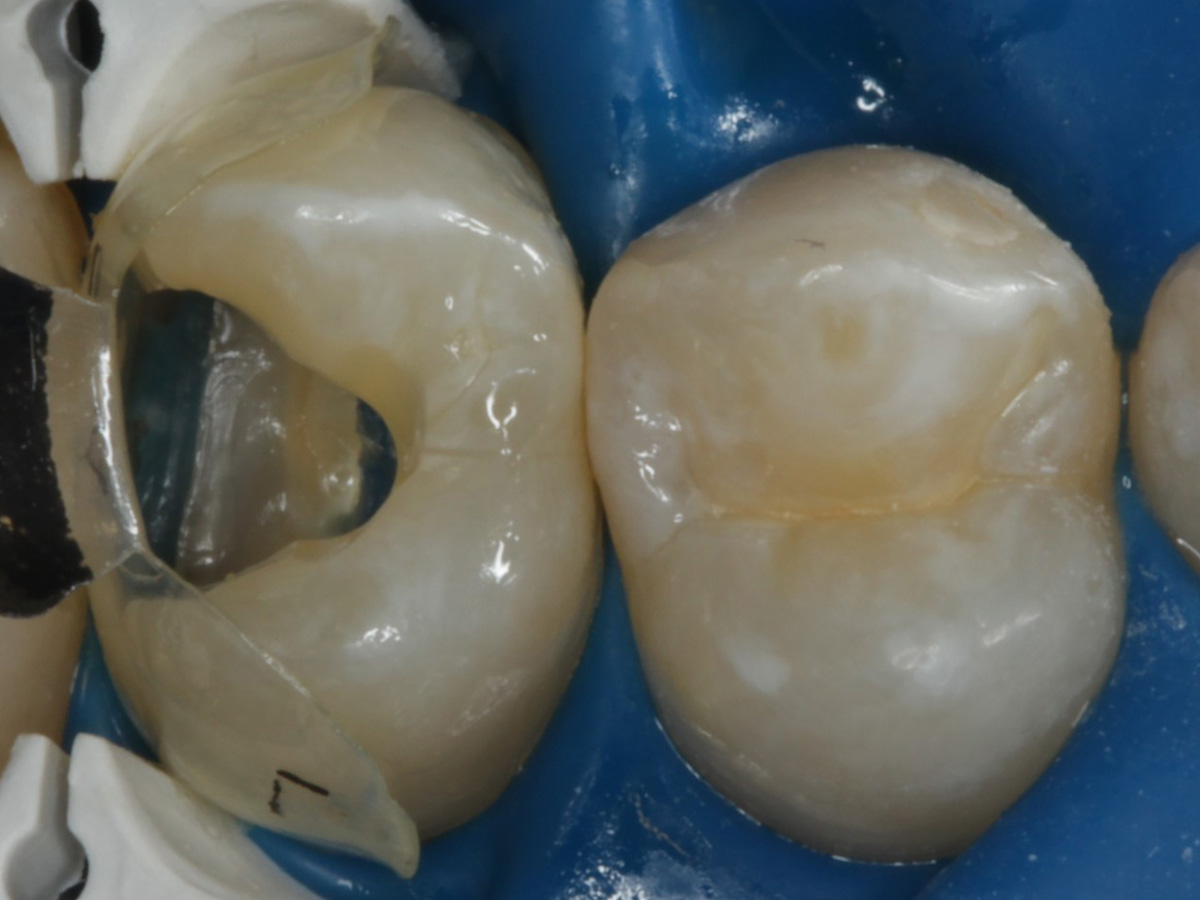

Abbildung 2

Intakte Kaufläche